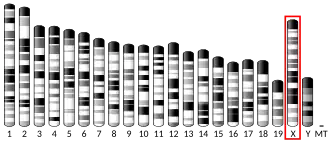

MECP2 (methyl CpG binding protein 2) is a gene[5] that encodes the protein MECP2.[6] MECP2 appears to be essential for the normal function of nerve cells. The protein seems to be particularly important for mature nerve cells, where it is present in high levels. The MECP2 protein is likely to be involved in turning off ("repressing" or "silencing") several other genes. This prevents the genes from making proteins when they are not needed. Recent work has shown that MECP2 can also activate other genes.[7] The MECP2 gene is located on the long (q) arm of the X chromosome in band 28 ("Xq28"), from base pair 152,808,110 to base pair 152,878,611.

MECP2 is an important reader of DNA methylation. Its methyl-CpG-binding (MBD) domain recognizes and binds 5-mC regions. MECP2 is X-linked and subject to X inactivation. MECP2 gene mutations are the cause of most cases of Rett syndrome, a progressive neurologic developmental disorder and one of the most common causes of cognitive disability in females.[8] At least 53 disease-causing mutations in this gene have been discovered.[9]